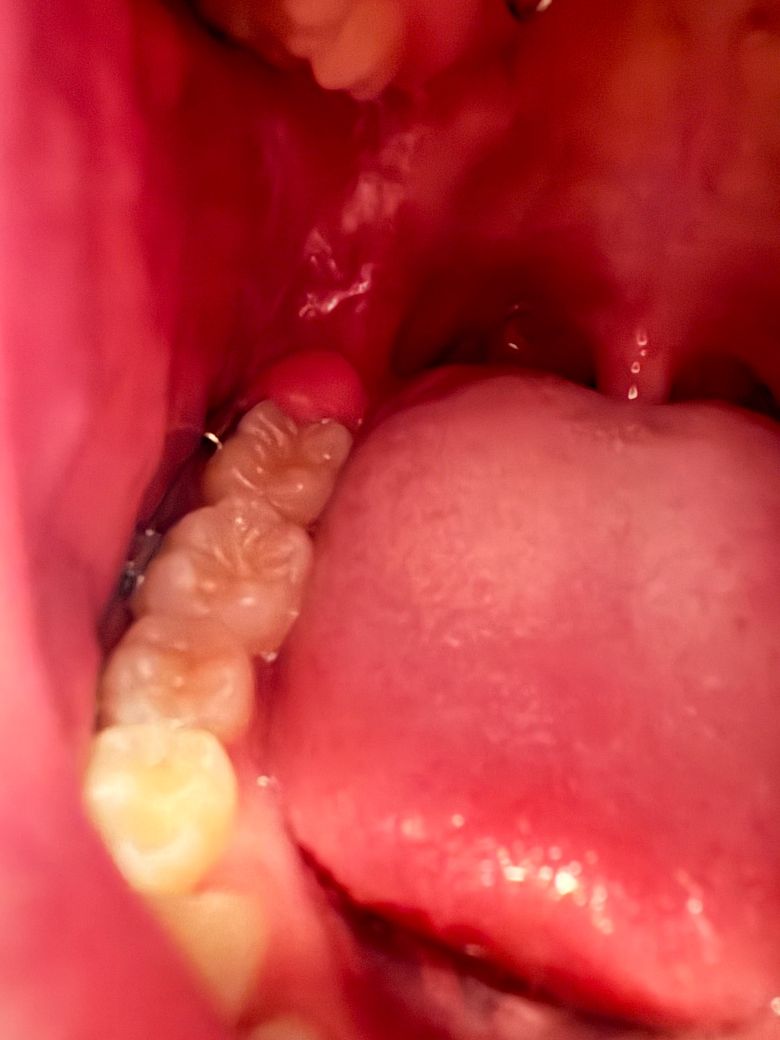

사랑니일까요 아니면 잇몸문제인가요?

어금니 뒷쪽 잇몸이 부었고 통증있고 씹을때 둔턱한? 느낌의 욱신거림이 있습니다

나이는 17살입니다(교정중, 엑스레이 찍을때 위아래 다 사랑니 있는 거 확인 했음)

사랑니로 인해서 염증이 크게 생긴 경우로 항생제 복용 및 발치가 필요한 상황으로 보입니다.

사랑니 때문에 잇몸에 염증이 생기는거 같습니다. 계속 불편하면 사랑니 발치를 하시는게 좋을것같습니다.

사랑니로 인한 치관주위염입니다. 사랑니가 맹출하면서 잇몸을 자극하고, 구강위생관리를 어렵게 해서 잇몸에 염증이 생긴겁니다